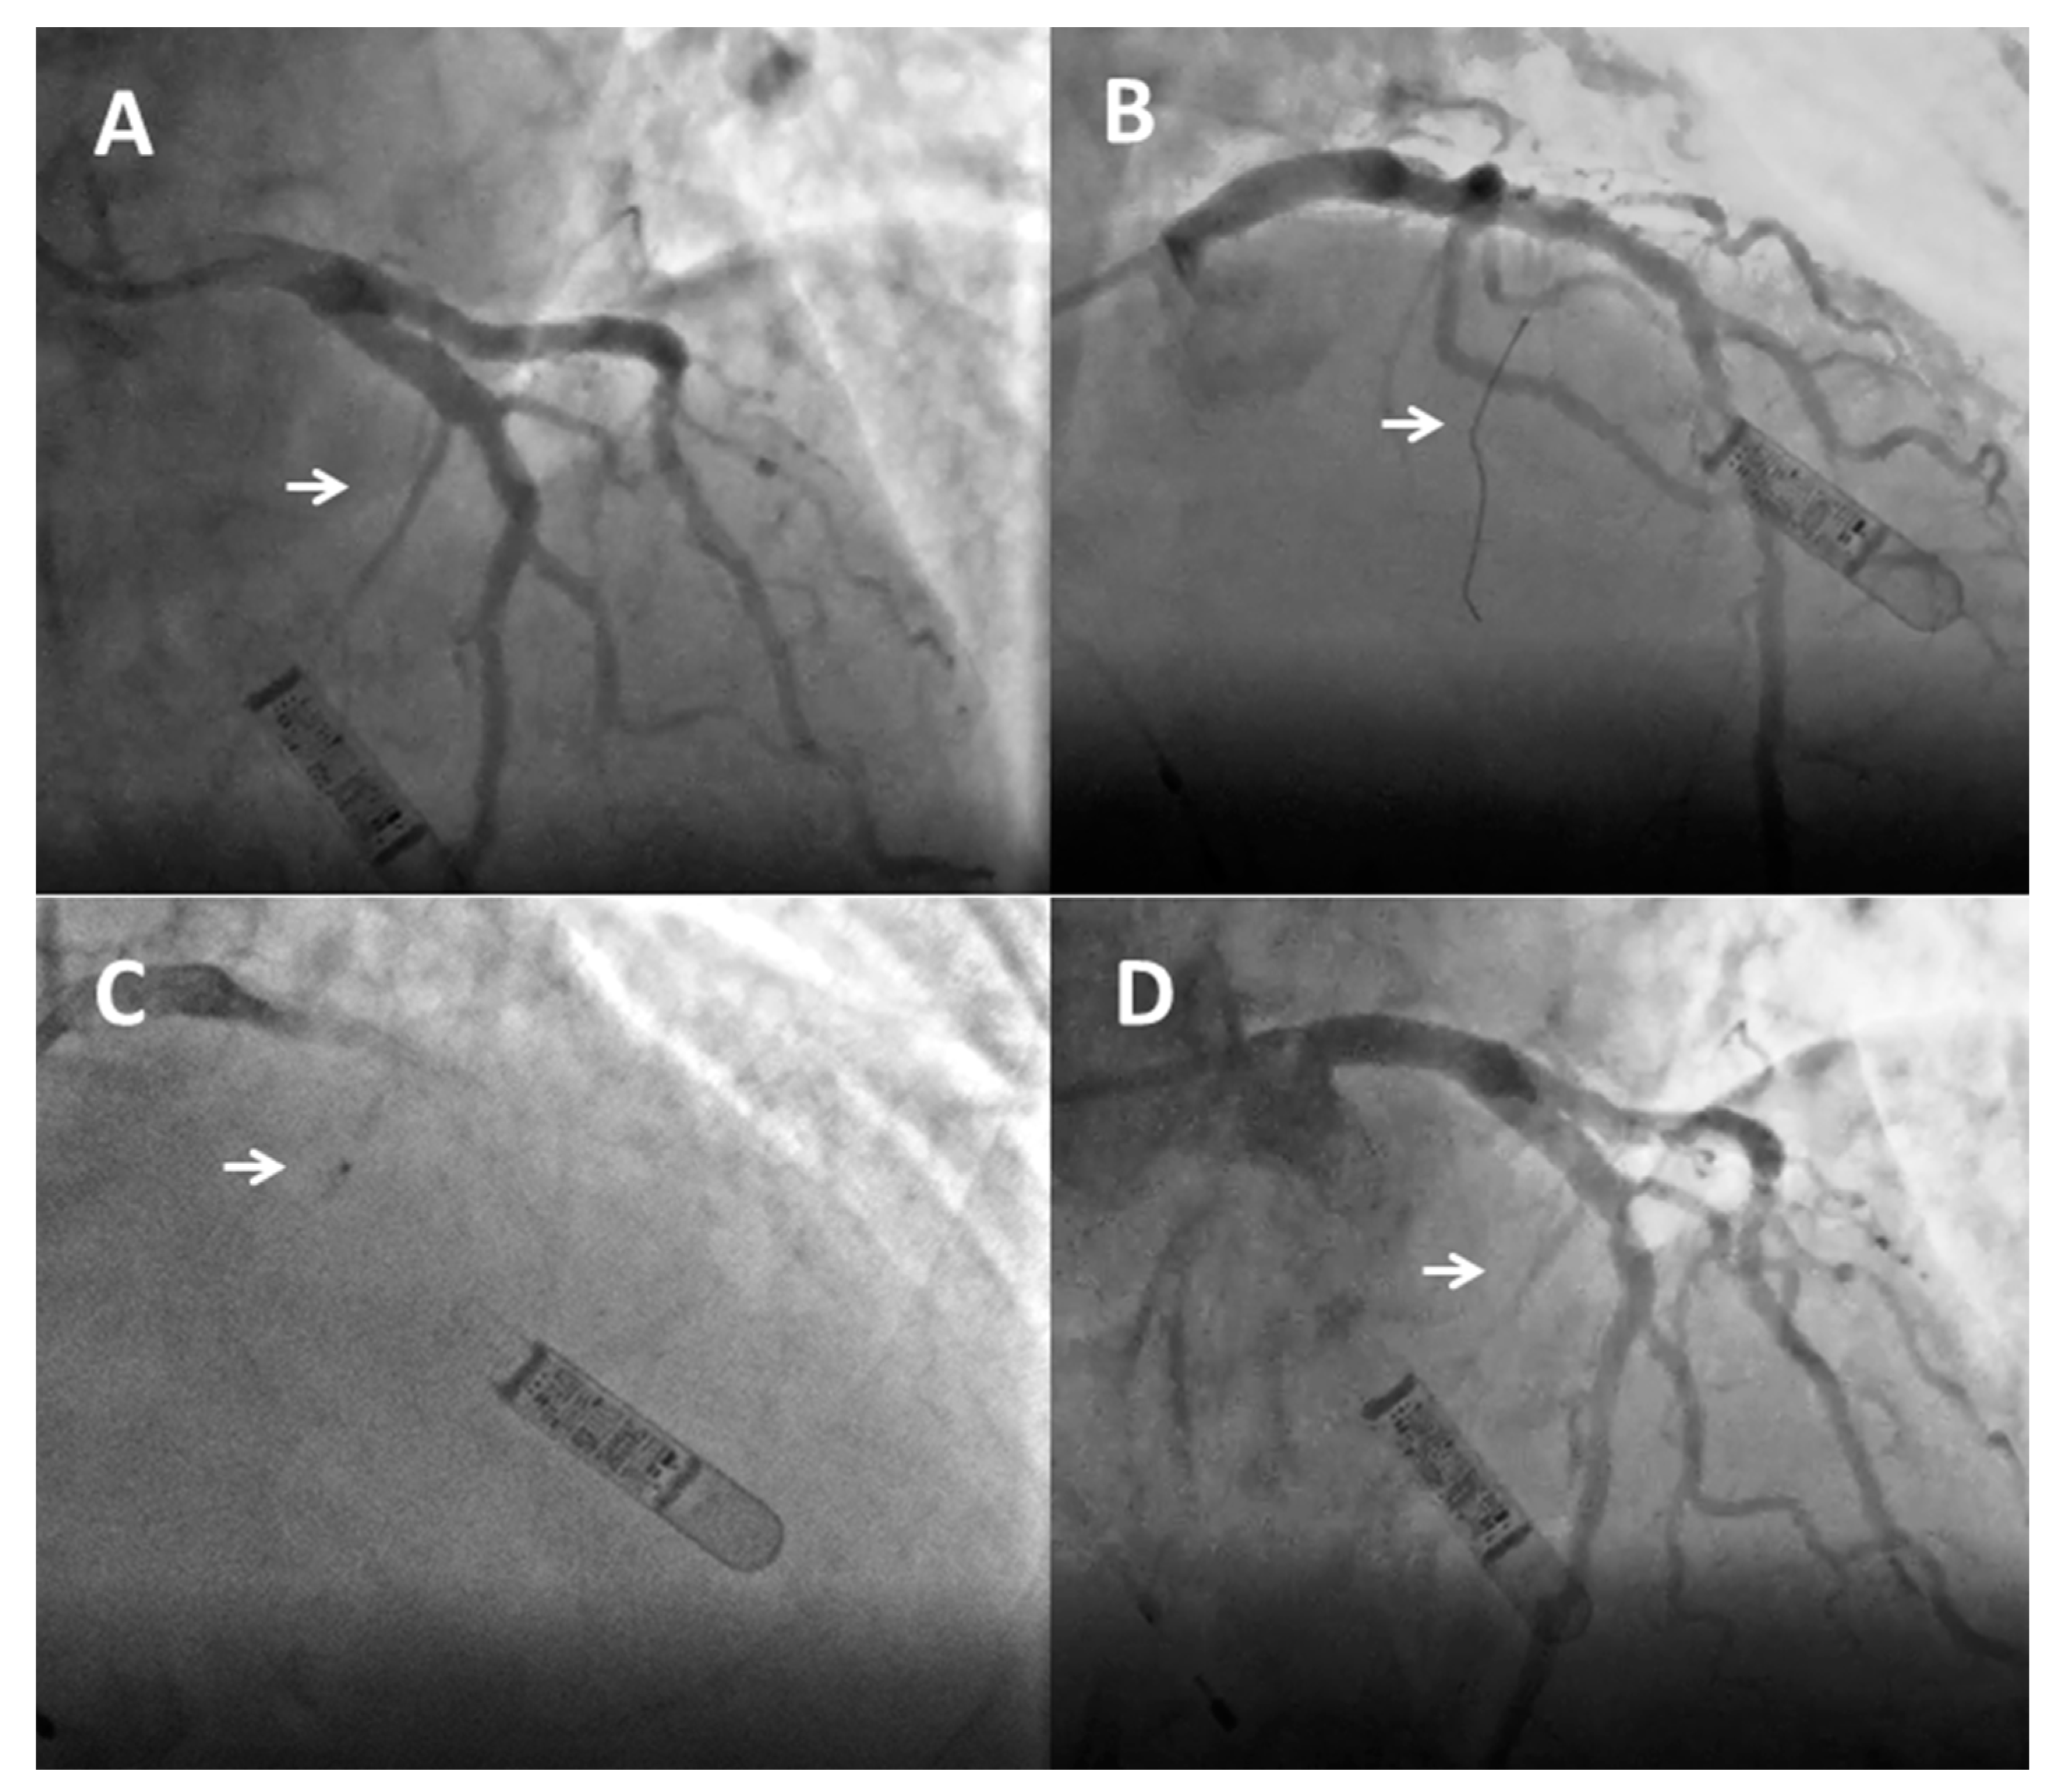

3.3. Description of the Procedure

- Pelliccia, F.; Niccoli, G.; Gragnano, F.; Limongelli, G.; Moscarella, E.; Andò, G.; Esposito, A.; Stabile, E.; Ussia, G.P.; Tarantini, G.; et al. Alcohol septal ablation for hypertrophic obstructive cardiomyopathy: A contemporary reappraisal. EuroIntervention 2019, 15, 411–417. [Google Scholar] [CrossRef]